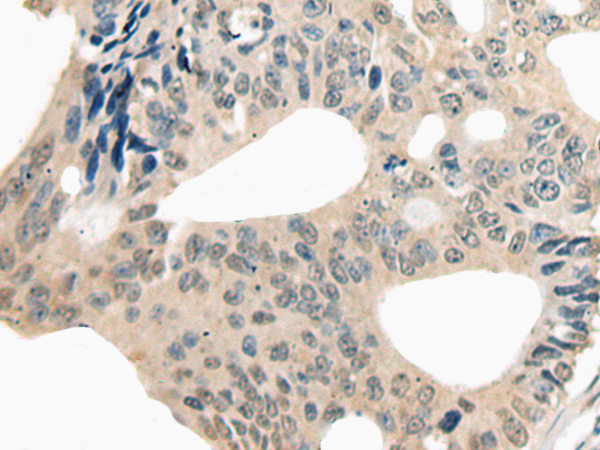

IHC positive control: |

Human colorectal cancer |

IHC Recommend dilution: |

20-100 |